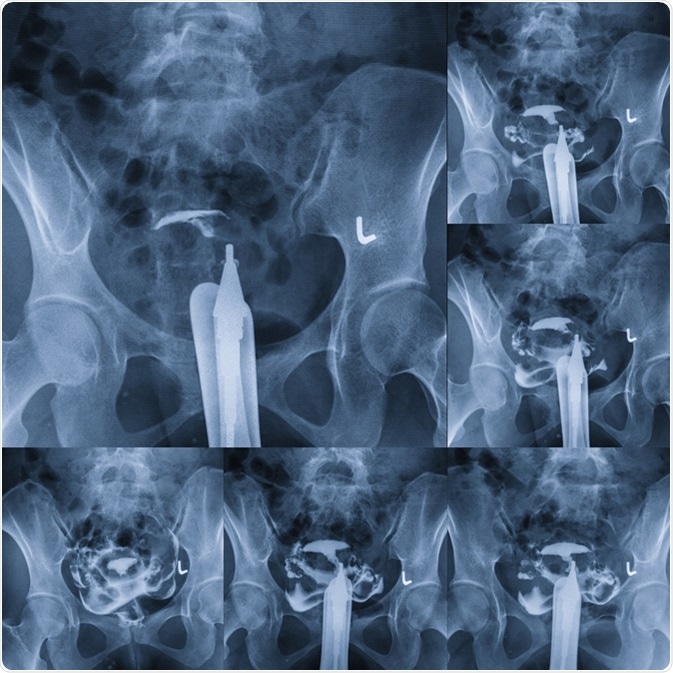

Hysterosalpingography - type of X-ray called fluoroscopy that looks at a woman

Hysterosalpingography - type of X-ray called fluoroscopy that looks at a woman's uterus and fallopian tubes. Image Credit: MossStudio / Shutterstock

An initial fluoroscopic image is taken to visualize the pelvis, after which the contrast is injected. Subsequently four images are taken at timed intervals to demonstrate the dye outlining the interior of the uterus, the filling of the fallopian tubes, and the potential spilling of the dye into the peritoneal cavity through the open or fimbrial end of each tube. This spill-over confirms tubal patency.

In some cases, no spillage is seen on one or both sides because of tubal spasm rather than blockage. To rule this out, in such cases an antispasmodic agent such as scopolamine is administered intravenously, followed by the injection of more contrast. More images are taken once the patient’s heart rate increases (which is another effect of this drug), showing that it is taking effect. The accumulated images record the early filling of the uterus, complete filling of the uterus, tubal filling, and spillage of the dye.